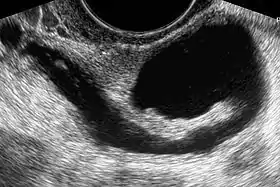

في حين أن اختبار وظائف الأنابيب في المرضي الذين يعانون من العقم البوقي غير ممكن، إلا أن اختبار السالكية البوقي ممكن، حيث أن تصوير الرحم بالصبغة سوف يظهر الأنبوب مفتوح عندما تنسكب الصبغة غير منفذو للإشعاع داخل تجويف البطن، ويمكن لتخطيط الصدى النسائي أن يظهر التشوهات، مثل موه البوق كمؤشر لانسداد الأنبوب. وأثناء الجراحة، خاصة تنظير البطن، يمكن معرفة حالة الأنابيب بواسطة صبغة ميثلين الزرقاء التي يمكن حقنها في الرحم بعملية تدعي تلوين البوق (chromotubation)، وتظهر أنها تمر إلي الأنابيب عندما يكون عنق الرحم مسدود. وقد وصفت عملية تلوين البوق بالمنظار كمعيار أساسي للتقييم البوقي.[3] وغالبا ما يرتبط مرض البوق بعدوى الكلاميديا، وقد أصبح اختبار الأجسام المضادة للكلاميديا وسيلة فحص فعالة من حيث التكلفة لأمراض البوق.[3]